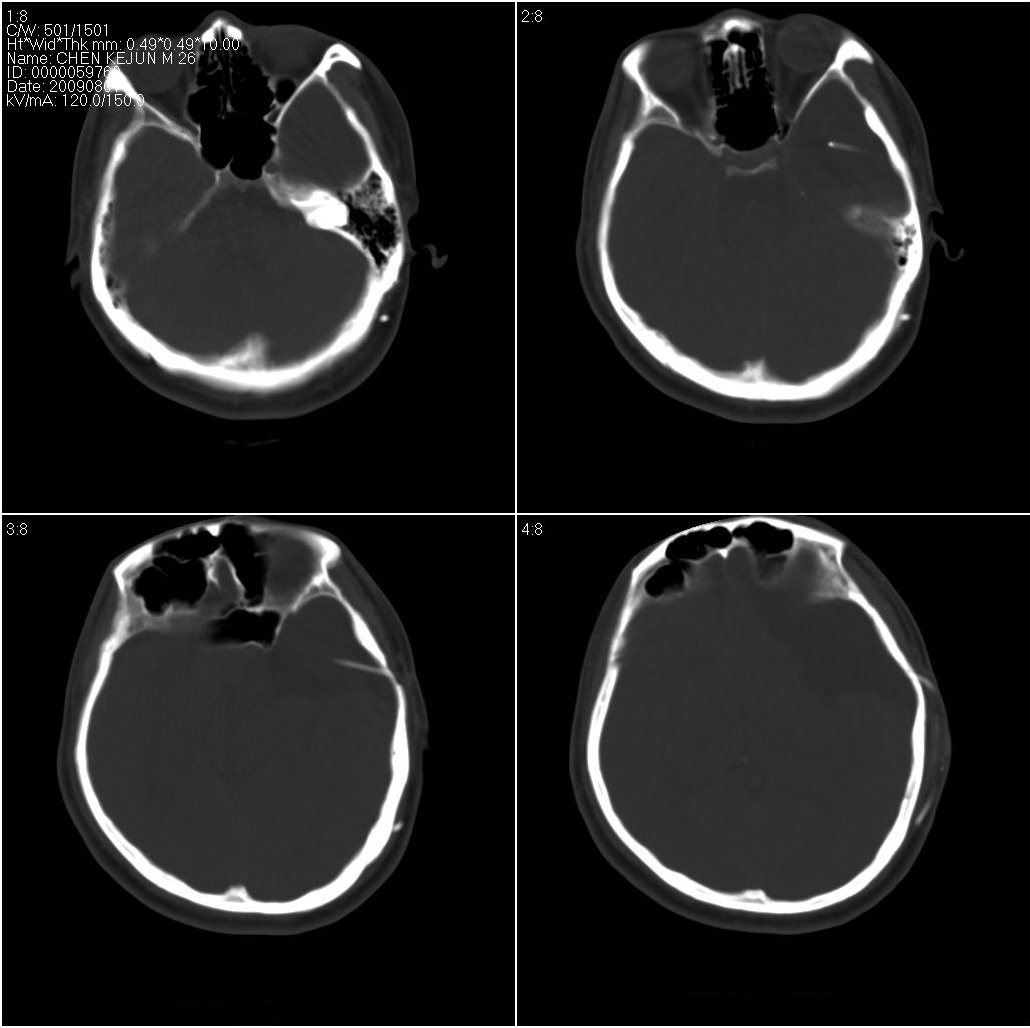

以下是引用随光逐影在2009-8-1 17:07:00的发言:[br]左侧中颅窝及左侧额颞顶部蛛网膜囊肿,并囊液引流术后。

以下是引用hhcckk在2009-8-1 17:29:00的发言:[br]左侧额颞部囊状低密度影,边缘平直,有明显占位效应,考虑蛛网膜囊肿,病变导致左额颞部受压,精神症状可与此有关,李松年编的ct诊断学上有过介绍,额叶联合区损害可引起智力、性格、精神症状,也就是9、10、11区[br][br]